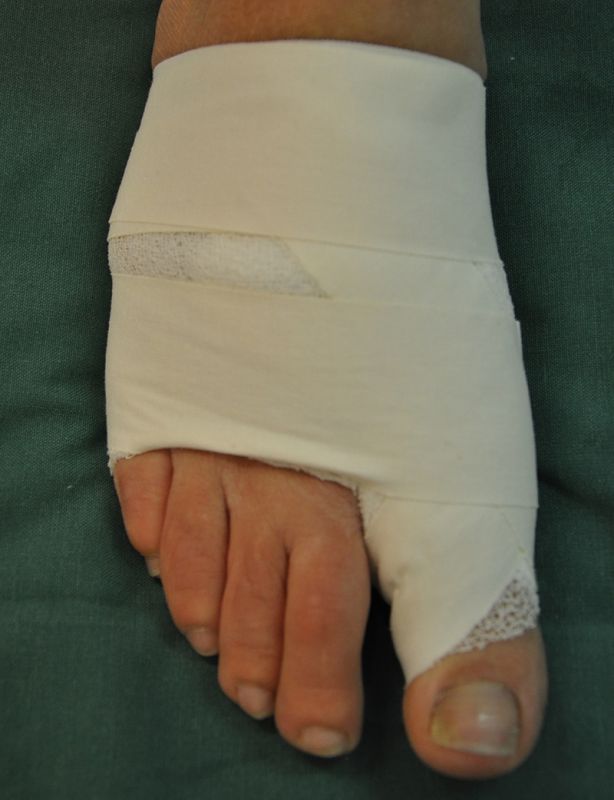

• Für das Anlegen des Spezialverbandes, entsprechendes Verbandsmaterial (sterile Kompressen, 4 cm Haftbinde, Pflaster oder Tapestreifen).

• Verbandswechsel (nur vom Operateur selbst oder durch speziell geschultes Personal) 7, 14, 21, 28 Tage postoperativ mit Freigabe nach 6 Wochen.